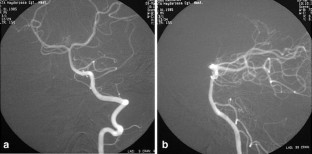

Brucellosis is a multisystem disease that may present with a large spectrum of clinical manifestations. Only five cases of intracranial aneurysm formation and/or subarachnoidal hemorrhage associated with brucellosis have been reported. In this paper, we take the opportunity to review these reports and present a new case of basilar artery aneurysm and subarachnoidal hemorrhage due to brucellosis.

Fig. 3